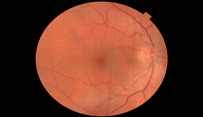

As well as the 3D scan, our instrument also takes a photograph of the eye in high resolution. This allows us to pin point any area of concern to review in depth.